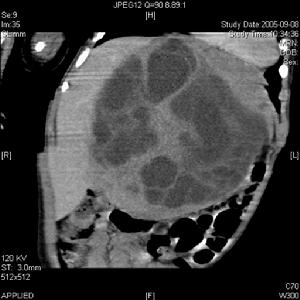

(5)轉移癌:轉移癌主要累及椎體或硬膜外組織,髓內轉移癌少見。髓內轉移癌占中樞神經系統轉移癌的1%來源包括:肺癌乳腺癌淋巴瘤結腸癌頭頸區腫瘤、腎上腺腫瘤等。以胸段最為常見,起病急影像學示病變較局限,長T1,長T2可見不規則強化

4.其他腫瘤:胚胎源性腫瘤及囊腫很少發生於髓內部位。脂肪瘤是最常見的胚胎髮育異常性腫瘤,大約占髓內腫瘤的1%這些並非為真性腫瘤起源於胚胎中胚層組織它們可因脂肪代謝沉積而增加在青壯年期增大並產生症狀,這些病變被認為是類髓內病變,因為它們通常位於軟膜下部位。轉移瘤約占髓內腫瘤的2%肺癌及乳腺癌是最常見的原發腫瘤來源。黑色素細胞瘤黑色素瘤、纖維肉瘤、黏液瘤亦為最常見的髓內轉移瘤。血管畸形,特別是海綿狀血管瘤亦被認為是髓內腫瘤。